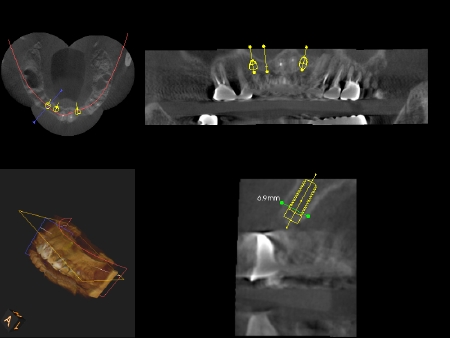

二つのCTシステム

通常の歯科医院ではあり得ない2つのCTを使い分けています。Galileos CTは全体を複雑細かに診断することができ、またトロフィーパンCT装置は被曝線量がごくわずかとしても知られており、体の負担を心配せずに診断していただけます。一回の撮影で5〜14マイクロシーベルトときわめて微量で安全です。1年間に私たちが自然界から浴びる放射線量が1000マイクロシーベルト以上と言われています。私たちの体はある程度の放射線によるダメージから治癒できる能力をもともと備えております。そのため5〜14マイクロシーベルトの微量な放射線は人体への負担はほとんどかかりません。